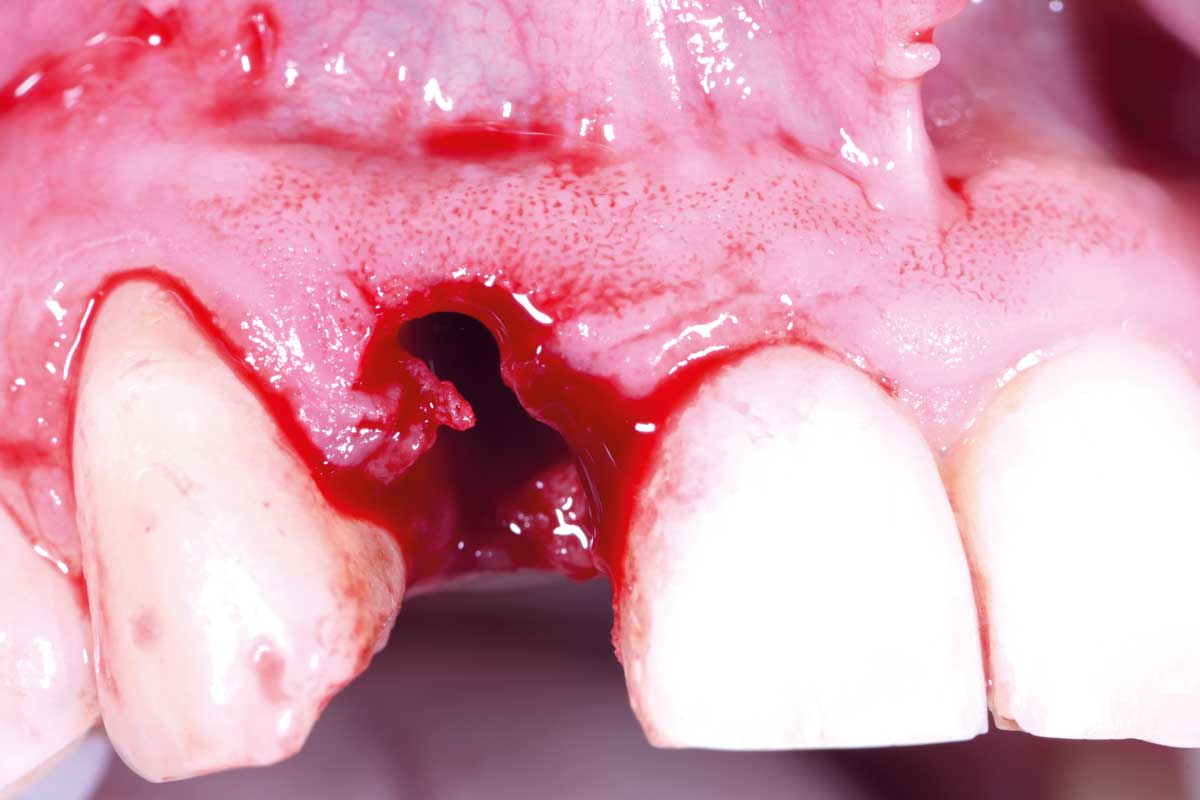

04/13 - Vertical extraction of tooth 12